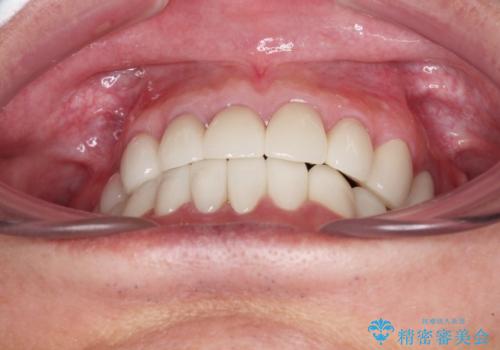

憧れの白い歯に 全顎セラミック治療

- 60歳を越え、黄ばんだ前歯をセラミッククラウンできれいな口元にしたいとのことで来院された患者様です。

診察したところ、前歯は反対咬合であり、その影響で抜歯が必要な奥歯があることが分かりました。

抜歯が必要な奥歯は、インプラント並びにブリッジにより補綴を行い、上下前歯は反対咬合を改善させるように補綴治療を行うこととしました。

健全な歯を削ってセラミッククラウンに置き換えることは、本来避けるべき治療と考えますが、今回は①患者様が60歳を越えていること、②要改善の咬合により抜歯が必要な奥歯があること、③反対咬合の前歯改善の手段としてセラミック治療が選択肢にあることなどから、全顎的なセラミック治療を行うこととしました。